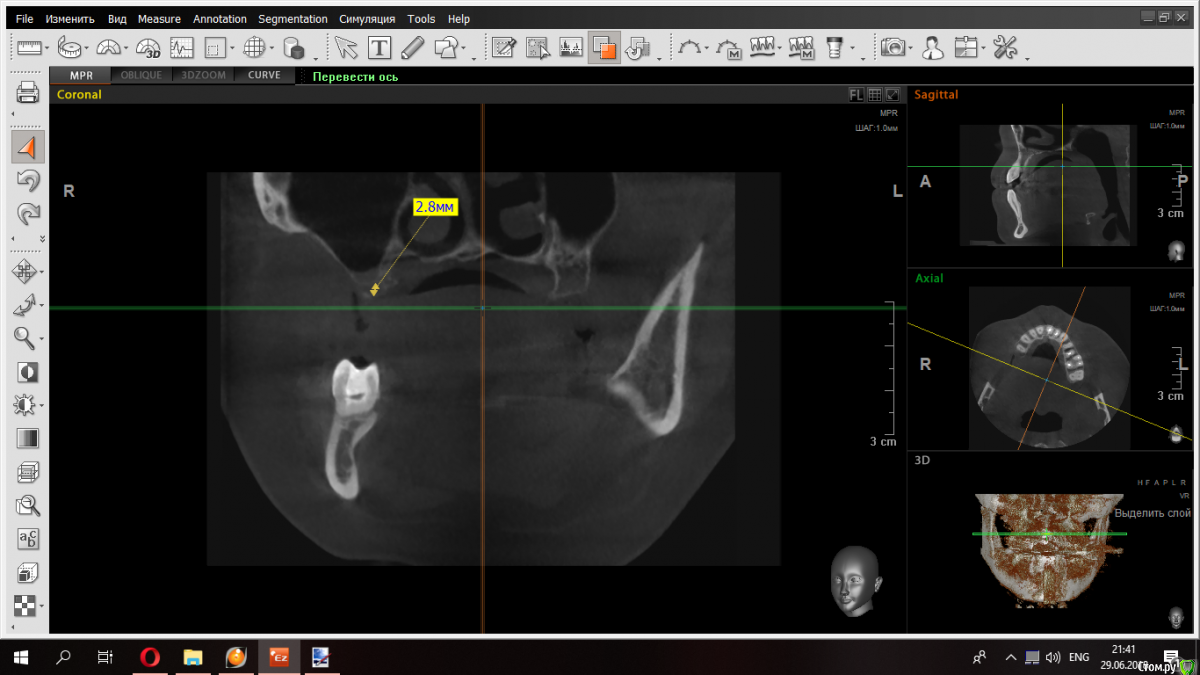

kramer Опубликовано 29 июня, 2018 Поделиться Опубликовано 29 июня, 2018 (изменено) Уважаемые коллеги, надеюсь на ваш совет по этому случаю. Какому способу аугментации вы бы отдали предпочтение? ОСЛ + НКР по вертикали с титановой сеткой? Если в области моляров еще можно было бы обойтись только синусов, то в области 15 совсем беда - ни высоты ни ширины. Срез 15Срез 16Срез 17 Изменено 29 июня, 2018 пользователем kramer Ссылка на комментарий